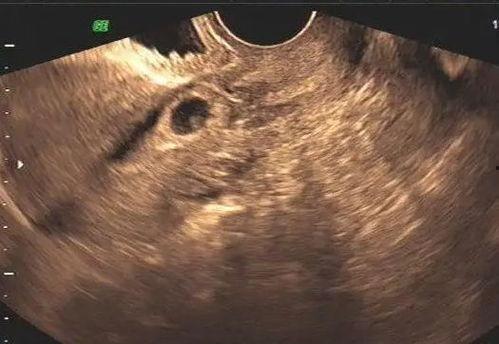

首先,让我们来了解怀孕肚子剧痛究竟是怎么回事。据《中国妇产科临床杂志》报道,怀孕期间,孕妇的子宫会逐渐增大,子宫壁也会变得更加敏感。当子宫收缩时,就会产生疼痛感。这种疼痛可能是轻微的,也可能是剧痛难忍。

1. 宫缩:随着孕周的增加,子宫收缩的频率和强度也会逐渐增加,导致孕妇感到疼痛。

2. 胎儿活动:胎儿在子宫内活动时,可能会撞击到子宫壁,引起疼痛。

4. 疾病因素:如胎盘早剥、子宫肌瘤等疾病,也可能引起肚子剧痛。